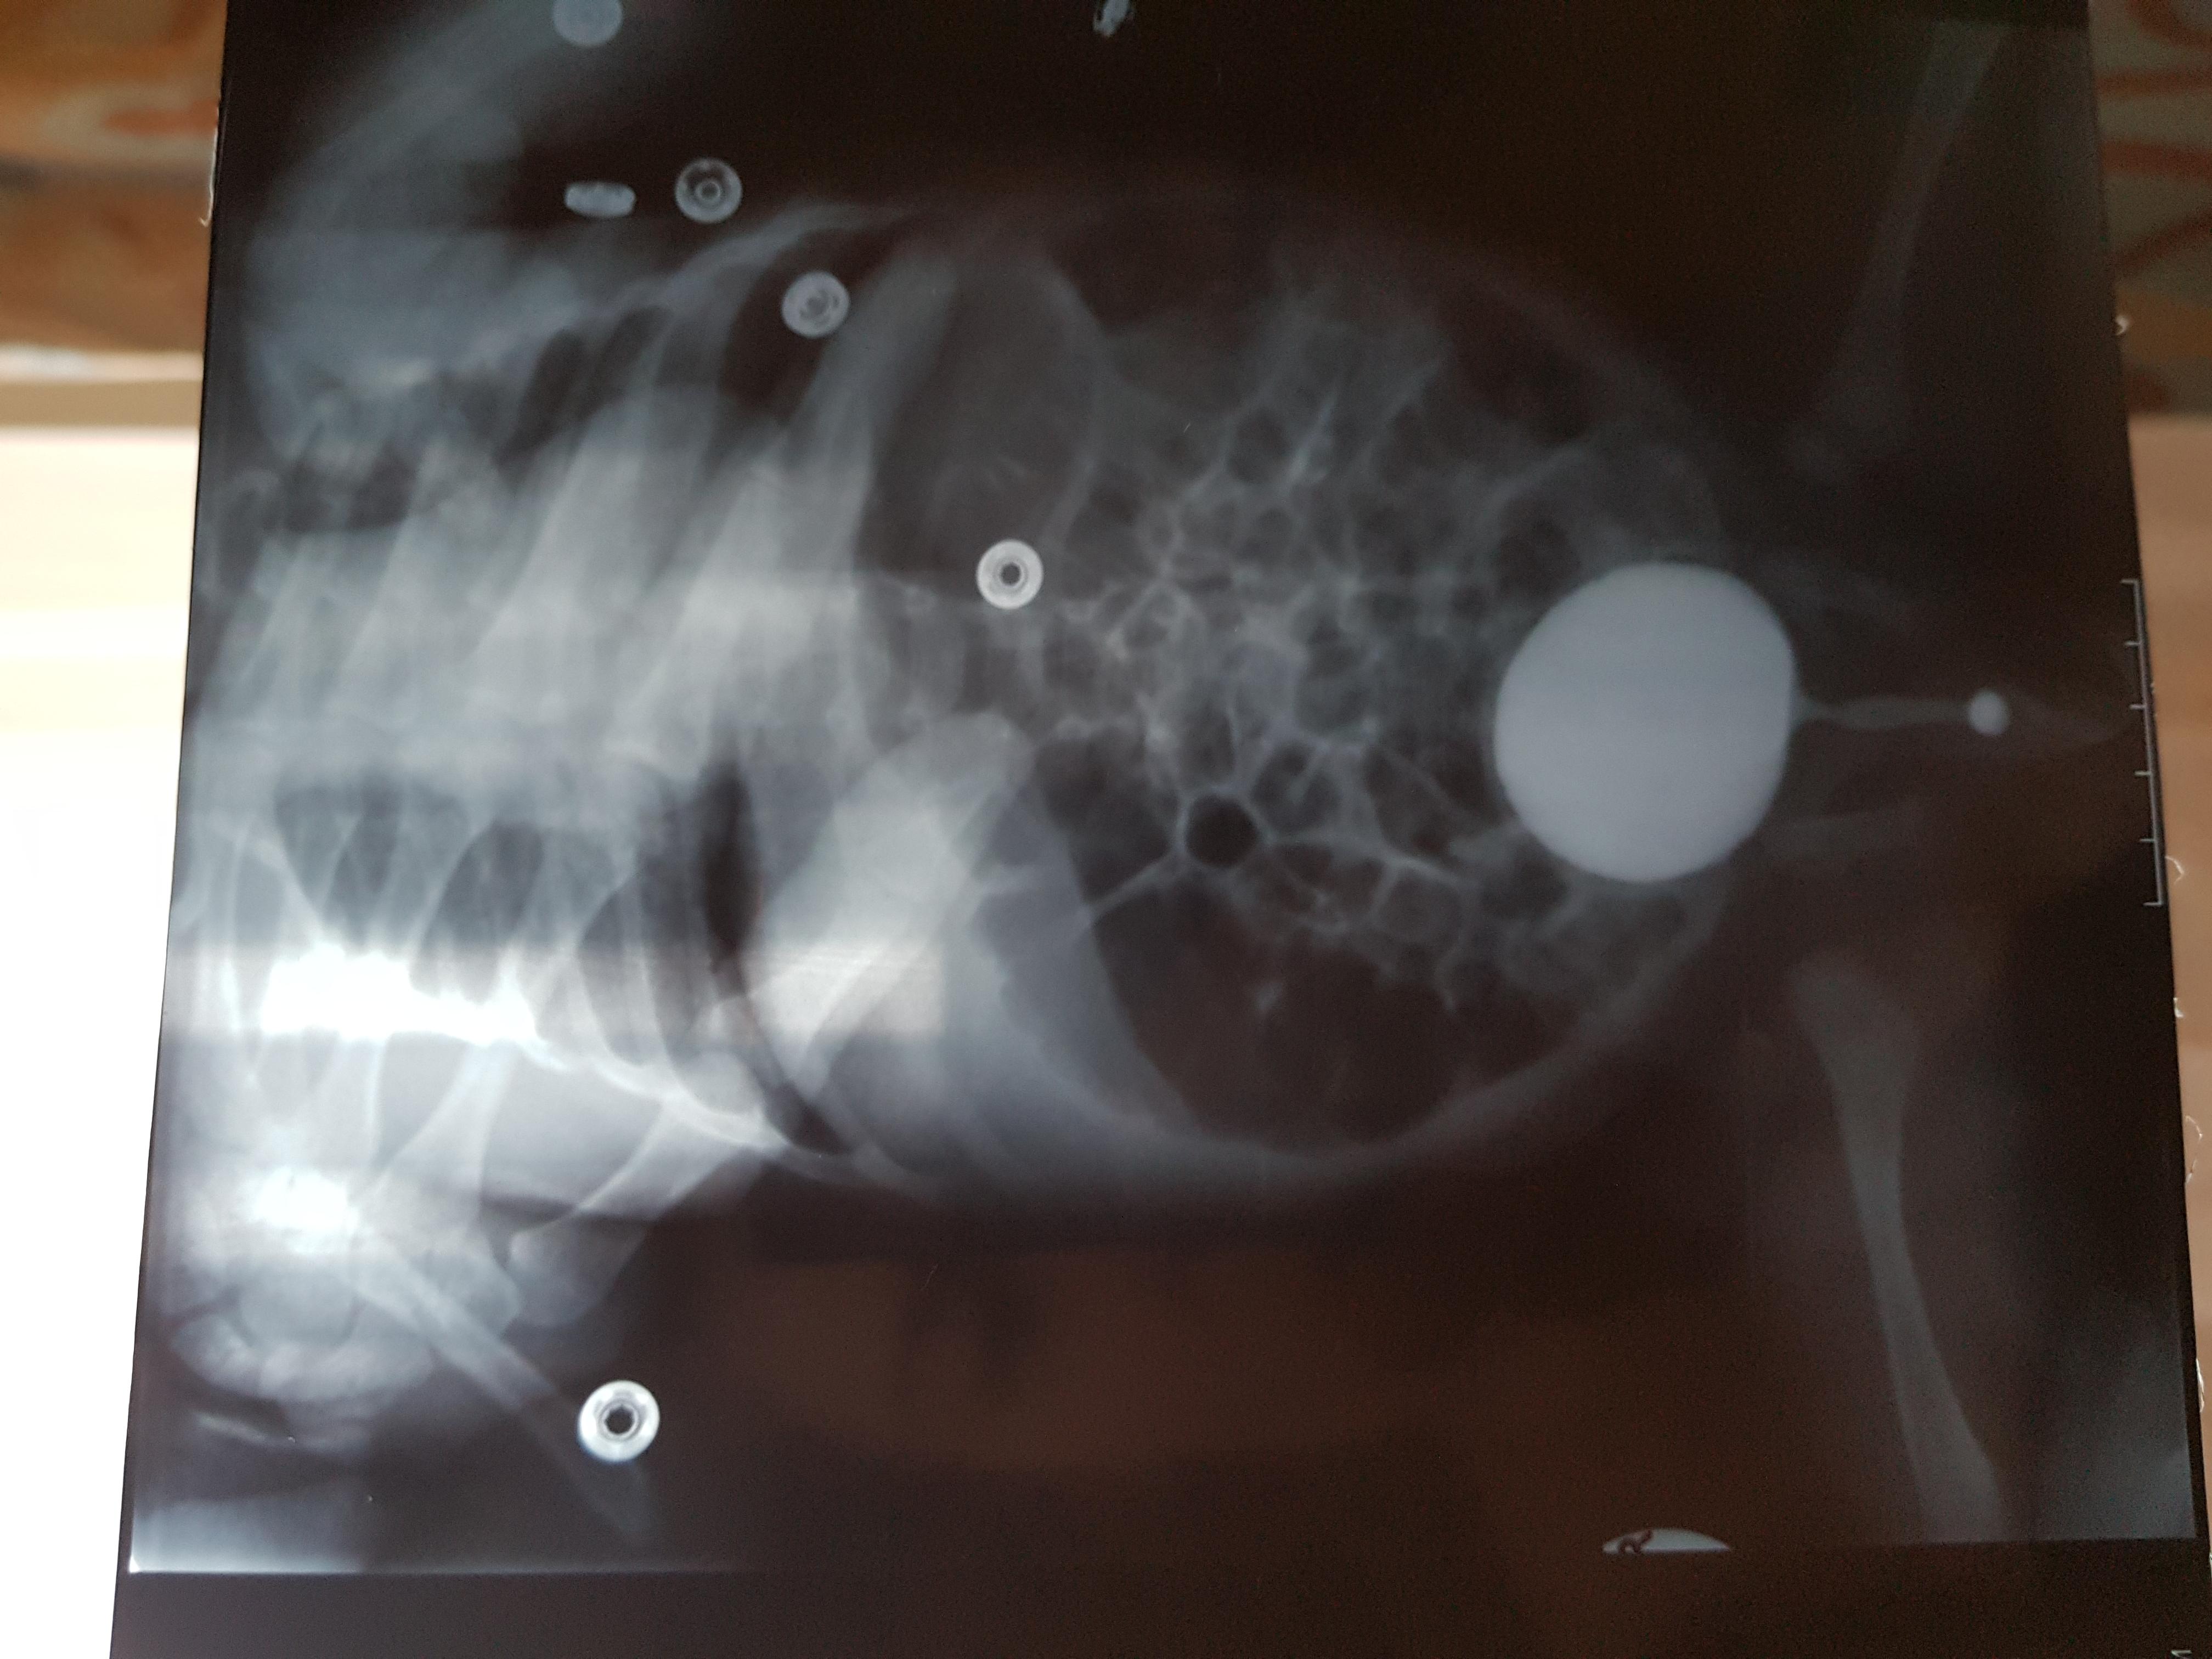

Болезнь Ормонда (ретроперитонеальный фиброз, забрюшинный фиброз) – хроническое воспаление жировой клетчатки забрюшинного пространства, которое постепенно приводит к компрессии и нарушению проходимости трубчатых структур данного анатомического участка. Чаще всего, в качестве этих тубулярных структур выступают мочеточники.

У меня есть сомнения, что причиной гидронефроза в Вашем случае явилось именно это состояние.

Возможно речь идет о пузырно-мочеточниковом рефлюксе.